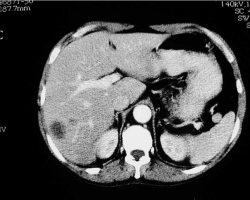

223. Artériopathie oblitérante de l'aorte, des artères viscérales et des membres inférieurs ; anévrysmes

Thrombose de l’aorte

2 août 2017